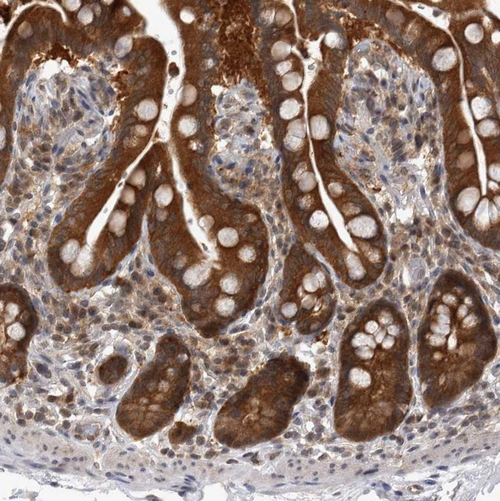

Immunohistochemical staining of human placenta shows moderate to strong nuclear and cytoplasmic positivity in trophoblastic cells.